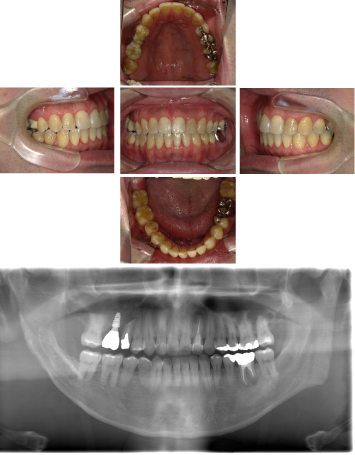

インプラント治療(左上5ソケット・GBR 右上2左上13GBR)

| 年代・性別 | 50代・男性 |

| 主訴 | 入れ歯だと咬めなくてつらい。 |

| 部位 | 上顎②1①2③4⑤Br |

| 治療期間 | 約9ヶ月 |

| 費用 | ¥1,794,100(税込) |

| 副作用・リスク |

|